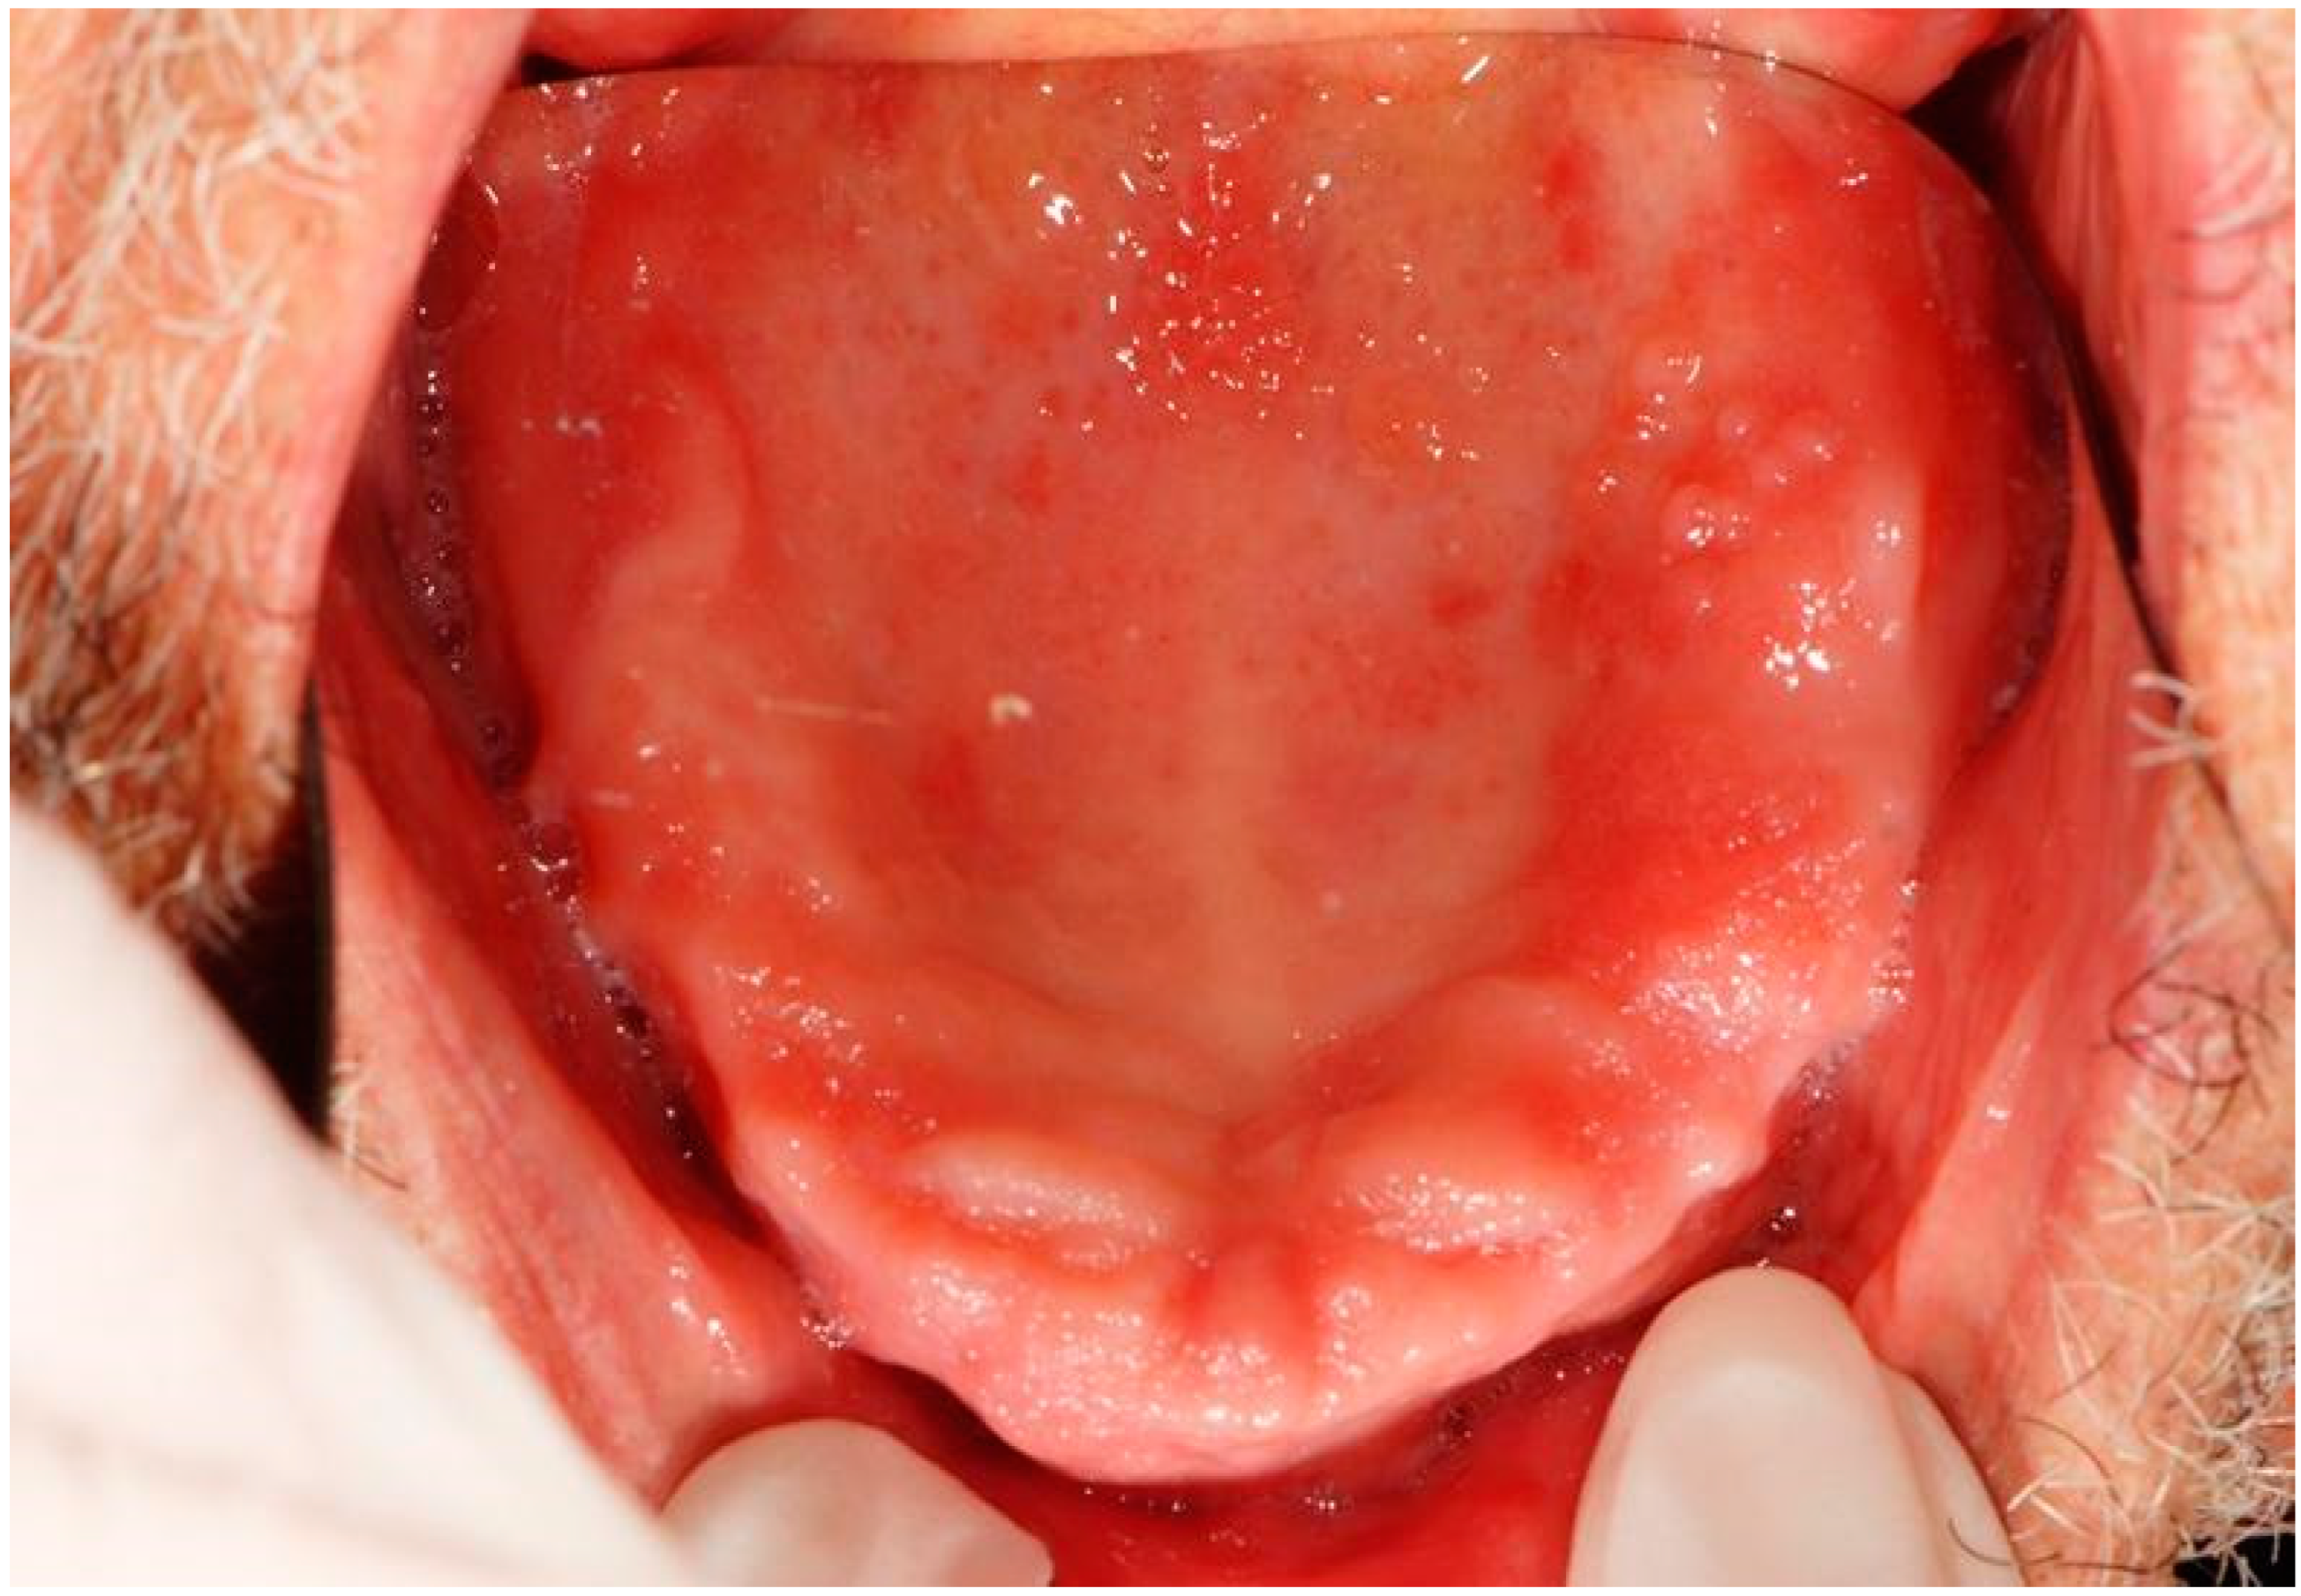

| 4 | Removable whitish plates Erythematous area Xerostomia | Candidiasis (pseudomembranous candidiasis, median rhomboid glossitis) | Dorsal tongue Oral mucous membranes | Nystatin Mucosamin® mouthwash | 3rd dose 9th dose |

| 13 | Erythematous area Ulcer Removable whitish plates | Epithelial atrophy without dysplasia Ulcer Candidiasis | Palate Tuberosity Dorsal tongue Alveolar process | Nystatin | 2nd dose 4th dose |